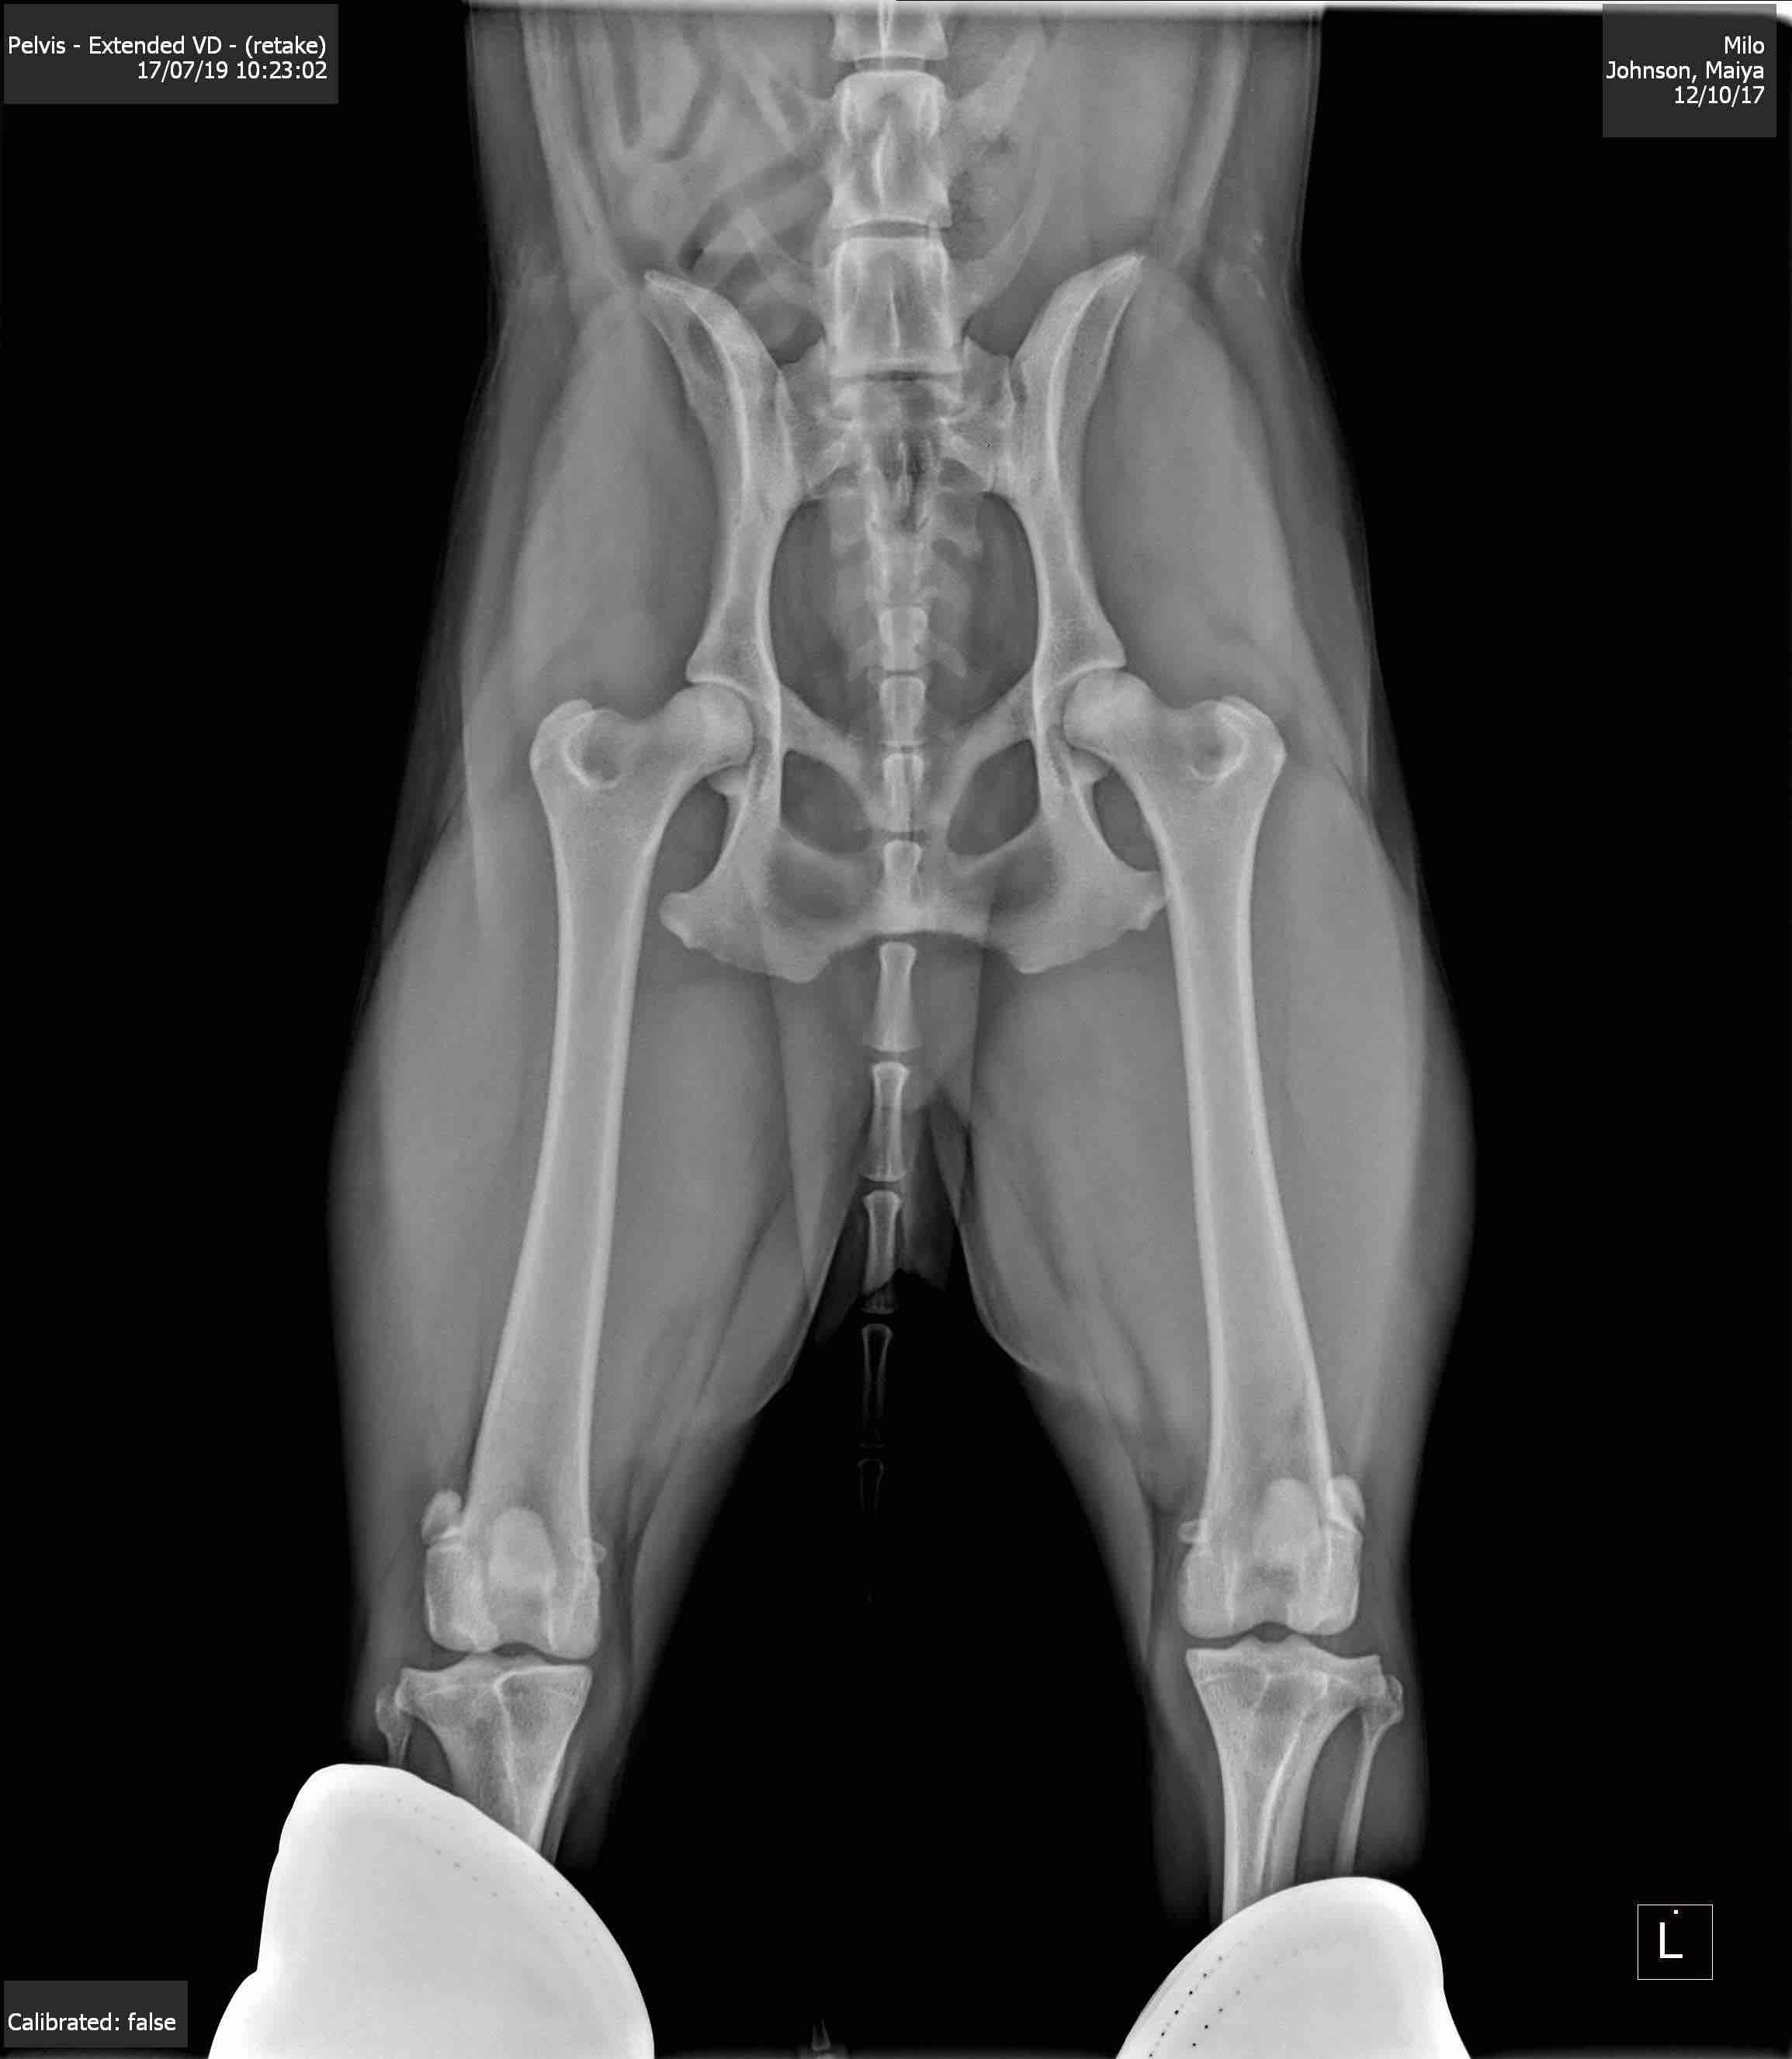

Pet's info: Dog | Australian Shepherd - miniature | Male | neutered | 1 year and 9 months old | 33 lbs

My pup recently had these rads taken, I’m looking to see what someone else sees in them and some prognosis. We’re trying to make educated next steps for the little guy. He’s so young.

Looks like mild hip dysplasia of the left hip. There also seems to be narrowing if the medial joint space in the right knee but this could be due to positioning. It would be easier to give you advice if you could give us more information about Milo’s clinical signs and what diagnosis your vet gave.